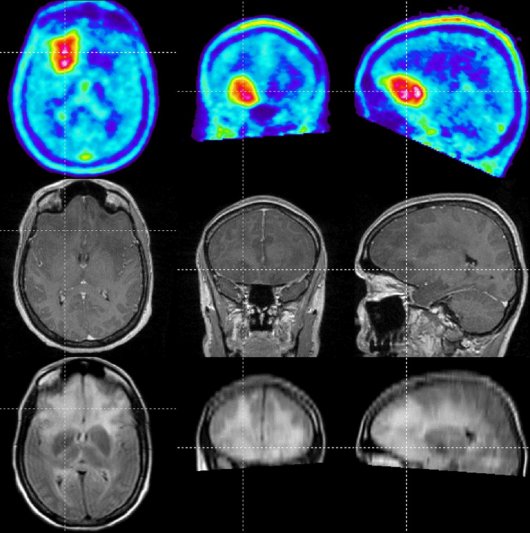

Hirntumore (Gliom, Glioblastom, Astrozytom) Neurochirurgie Universitätsmedizin Göttingen. Hirntumor Forum : MRT ohne Kontrastmittel ausreichend? Unterstützen Sie unsere Arbeit für Hirntumorpatienten (Ich bin hier nicht die einzige, die mehr als 30 MRT mit Kontrastmittel hatte, wodurch mehrere Tumore erkannt und erfolgreich therapiert wurden

MRTUntersuchungen am Kopf das erwartet Sie Privat Radiologie Regensburg. Wenn der Tumor oder die Region des Tumors vorher Kontrastmittel einlagerte und jetzt nicht mehr ist dies im Allgemeinen ein gutes Zeichen, ansonsten bedeutet es nur, dass die Bluthirnschranke in Ordnung ist. Ohne Kontrastmittel-MRTs wäre ich wegen der Tumore nicht mehr am Leben.) Tumore wachsen, weil sich einzelne Zellen teilen.